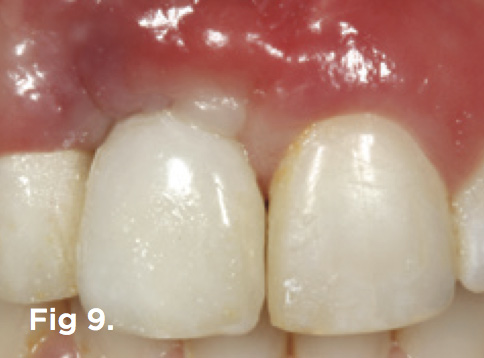

Fig 9. The mucosal tissue was nonsurgically sculpted with pressure through subgingival contour to the temporary restoration.

Figure 9